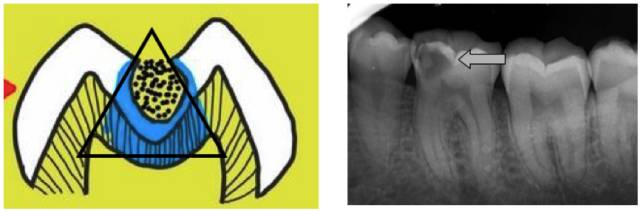

牙齿的解剖结构使得龋坏往往呈现口小底大的三角形。我们肉眼中所看到的小洞可能只是三角形的一个顶点。很多患者经常说的,咬到硬物后突然发现牙齿有了一个大洞,往往都是那些「看起来很小」的洞,其周边的牙体组织已经十分薄弱,稍一受力便土崩瓦解的结果。

还有些龋坏位于两颗牙之间,临床上称之为邻面龋,表面上看起来完好无损,但一拍牙片,问题就暴露无遗。这样的龋坏起初可能只表现为食物嵌塞。若不及时进行牙线清洁,定期检查治疗,就会逐渐出现食物嵌塞疼、冷热刺激疼等症状,此时牙缝间可能已形成了较深的龋坏。